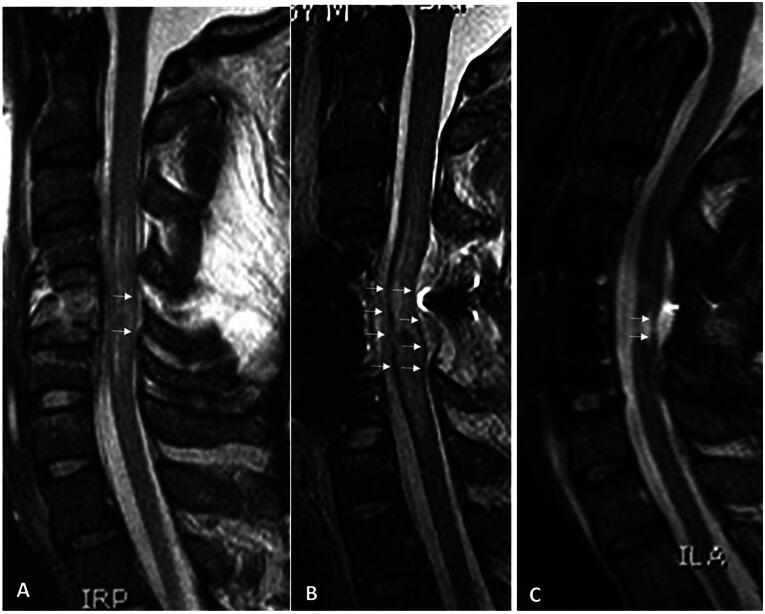

脊髓损伤(SCI)仍然是一个主要的未解决的问题,它永久性地损害了全世界无数人的生命。尽管SCI的基础、临床前和临床科学的进步为患者带来了希望,但临床医生可能缺乏对相关细胞和分子事件的全面了解,实验室研究人员可能低估了细胞和分子现象如何转化为有意义的功能结果。为了帮助弥合这些观点,我们首先回顾了美国脊髓损伤协会(ASIA)损伤量表(AIS)分级,这是衡量脊髓损伤临床结果的主要工具,以及临床上重要的AIS分级“转换”(改善)概念,这发生在一些但不是所有患者身上。然后,我们回顾了导致AIS分级及其转化的潜在机制,包括短暂性神经功能障碍机制(神经元和轴突“昏迷”)、继发性细胞损失机制(凋亡、焦亡和坏死)和轴突损失机制(原发性轴突切断和继发性轴突变性)。最后,我们简要回顾了可能改善脊髓损伤后继发性组织损失和神经功能障碍机制的临床治疗方法。

Spinal cord injury (SCI) remains a major unsolved problem that permanently impairs the lives of innumerable individuals worldwide. Although advances in the basic, pre-clinical and clinical sciences of SCI hold promise for patients, clinicians may lack a full insight into the relevant cellular and molecular events, and laboratory researchers may underappreciate how cellular and molecular phenomena translate into meaningful functional outcomes. To help bridge these perspectives, we first review the American Spinal Injury Association (ASIA) Impairment Scale (AIS) grade, which is the principal instrument used to gauge clinical outcomes in SCI, and the clinically important concept of AIS grade "conversion" (improvement), which occurs in some but not all patients. We then review underlying mechanisms that contribute to the AIS grade and its conversion, including mechanisms of transient neurological dysfunction (neuronal and axonal "stunning"), mechanisms of secondary cell loss (apoptosis, pyroptosis, and necroptosis), and mechanisms of axonal loss (primary axotomy and secondary axonal degeneration). Finally, we briefly review approaches to clinical management that may ameliorate identified mechanisms of secondary tissue loss and neurological dysfunction following SCI.